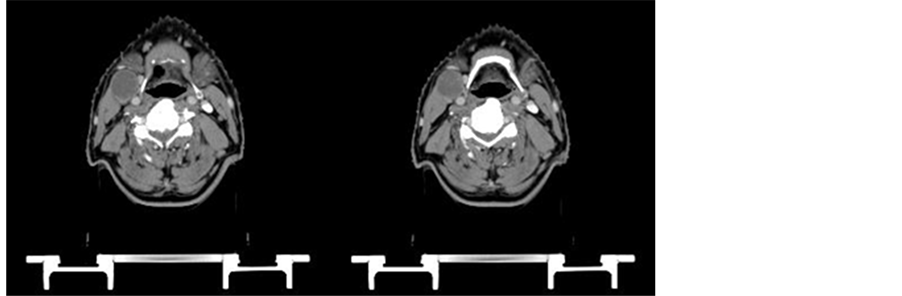

on oral examination. FNAC (fine needle aspiration cytology) from the neck node was reported as moderately differentiated squamous cell carcinoma. A panendoscopy was done to search for the primary. Even a CT scan failed to pick up the primary disease site. The patient was started on weekly cisplatin 40 mg/m2 and nimotuzumab 200 mg for 6 weekly cycles. Radiation was delivered to a total dose of 66 Gy/33 fractions/6½ weeks. CT scan done six weeks after the completion of RT showed regression of the nodal mass to 3 cm × 2 cm (partial response). PET CT was done to see the functional uptake and PET CT showed uptake (Figure 4). A radical neck dissection was performed for the residual node and the histopathological examination of lymph node did

Figure 4. (a) Pre-treatment CECT of neck showing large neck node measuring 7 cm × 6 cm with central necrosis; (b) Post treatment CT scan―Follow up CECT shows significant residual disease measuring 3 cm × 2 cm.

not reveal any residual disease. This shows the complete pathological response to treatment. Patient was followed up for 18 months.

2.5. Case 5

A 72-year-old gentleman presented with swelling on the right side of neck (3.5 cm × 1.8 cm) for 3 months duration. Oral examination showed a growth involving the right side of the soft palate and tonsillar region that was firm on palpation and measured 4 cm × 3 cm approximately. He was diagnosed to have Carcinoma Oropharynx T2N2M0. He received 6 cycles of injection carboplatin 150 mg (in view of high creatinine levels of 1.9 mg) and 200 mg of nimotuzumab along with radiotherapy delivered by IMRT technique to a dose of 6600 cGy/33 fractions/6½ weeks. A follow-up PET scan done after the completion of treatment showed complete regression of primary and nodal disease (Figure 5).

Figure 5. (a) Pretreatment PET CT scan showing 4 cm × 3 cm mass in the right soft palate and the tonsillar region; (b) Post treatment PET-CT scan showing complete regression of primary and nodal disease.